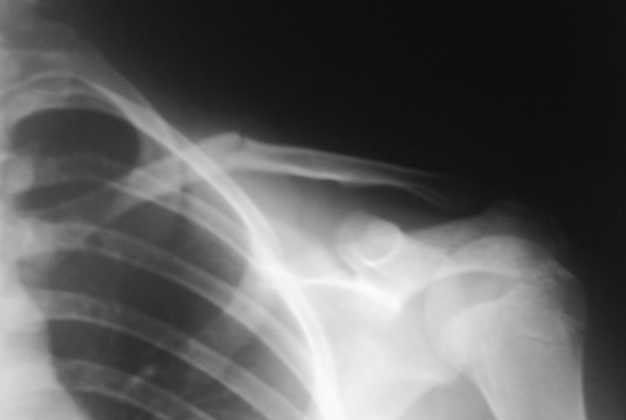

Девочка 14 лет, на даче упала с турника 05-07-08, в наш травмпункт

обратились на следующий день - Диагноз: Закрытый перлом диафиза левой

ключицы. Дежурным травматологом наложена 8-образная гипсовая повязка.

Сегодня произведен контрольный снимок.